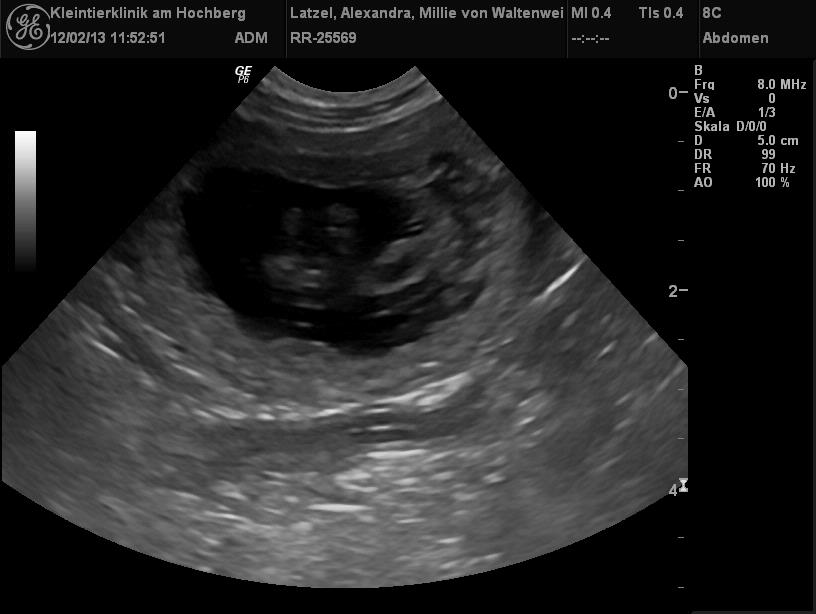

| Hier die Ultraschallbilder zum Beweis |

| Hurra, Millie ist schwanger! |

| Millie war zum Decken bei Vincent vow for verity von der kleinen Arche!

Sie sind ein wirklich schönes Paar! Nun freuen wir uns sehr auf die Welpis aus dieser Verbindung, die wir Mitte Juli erwarten! |